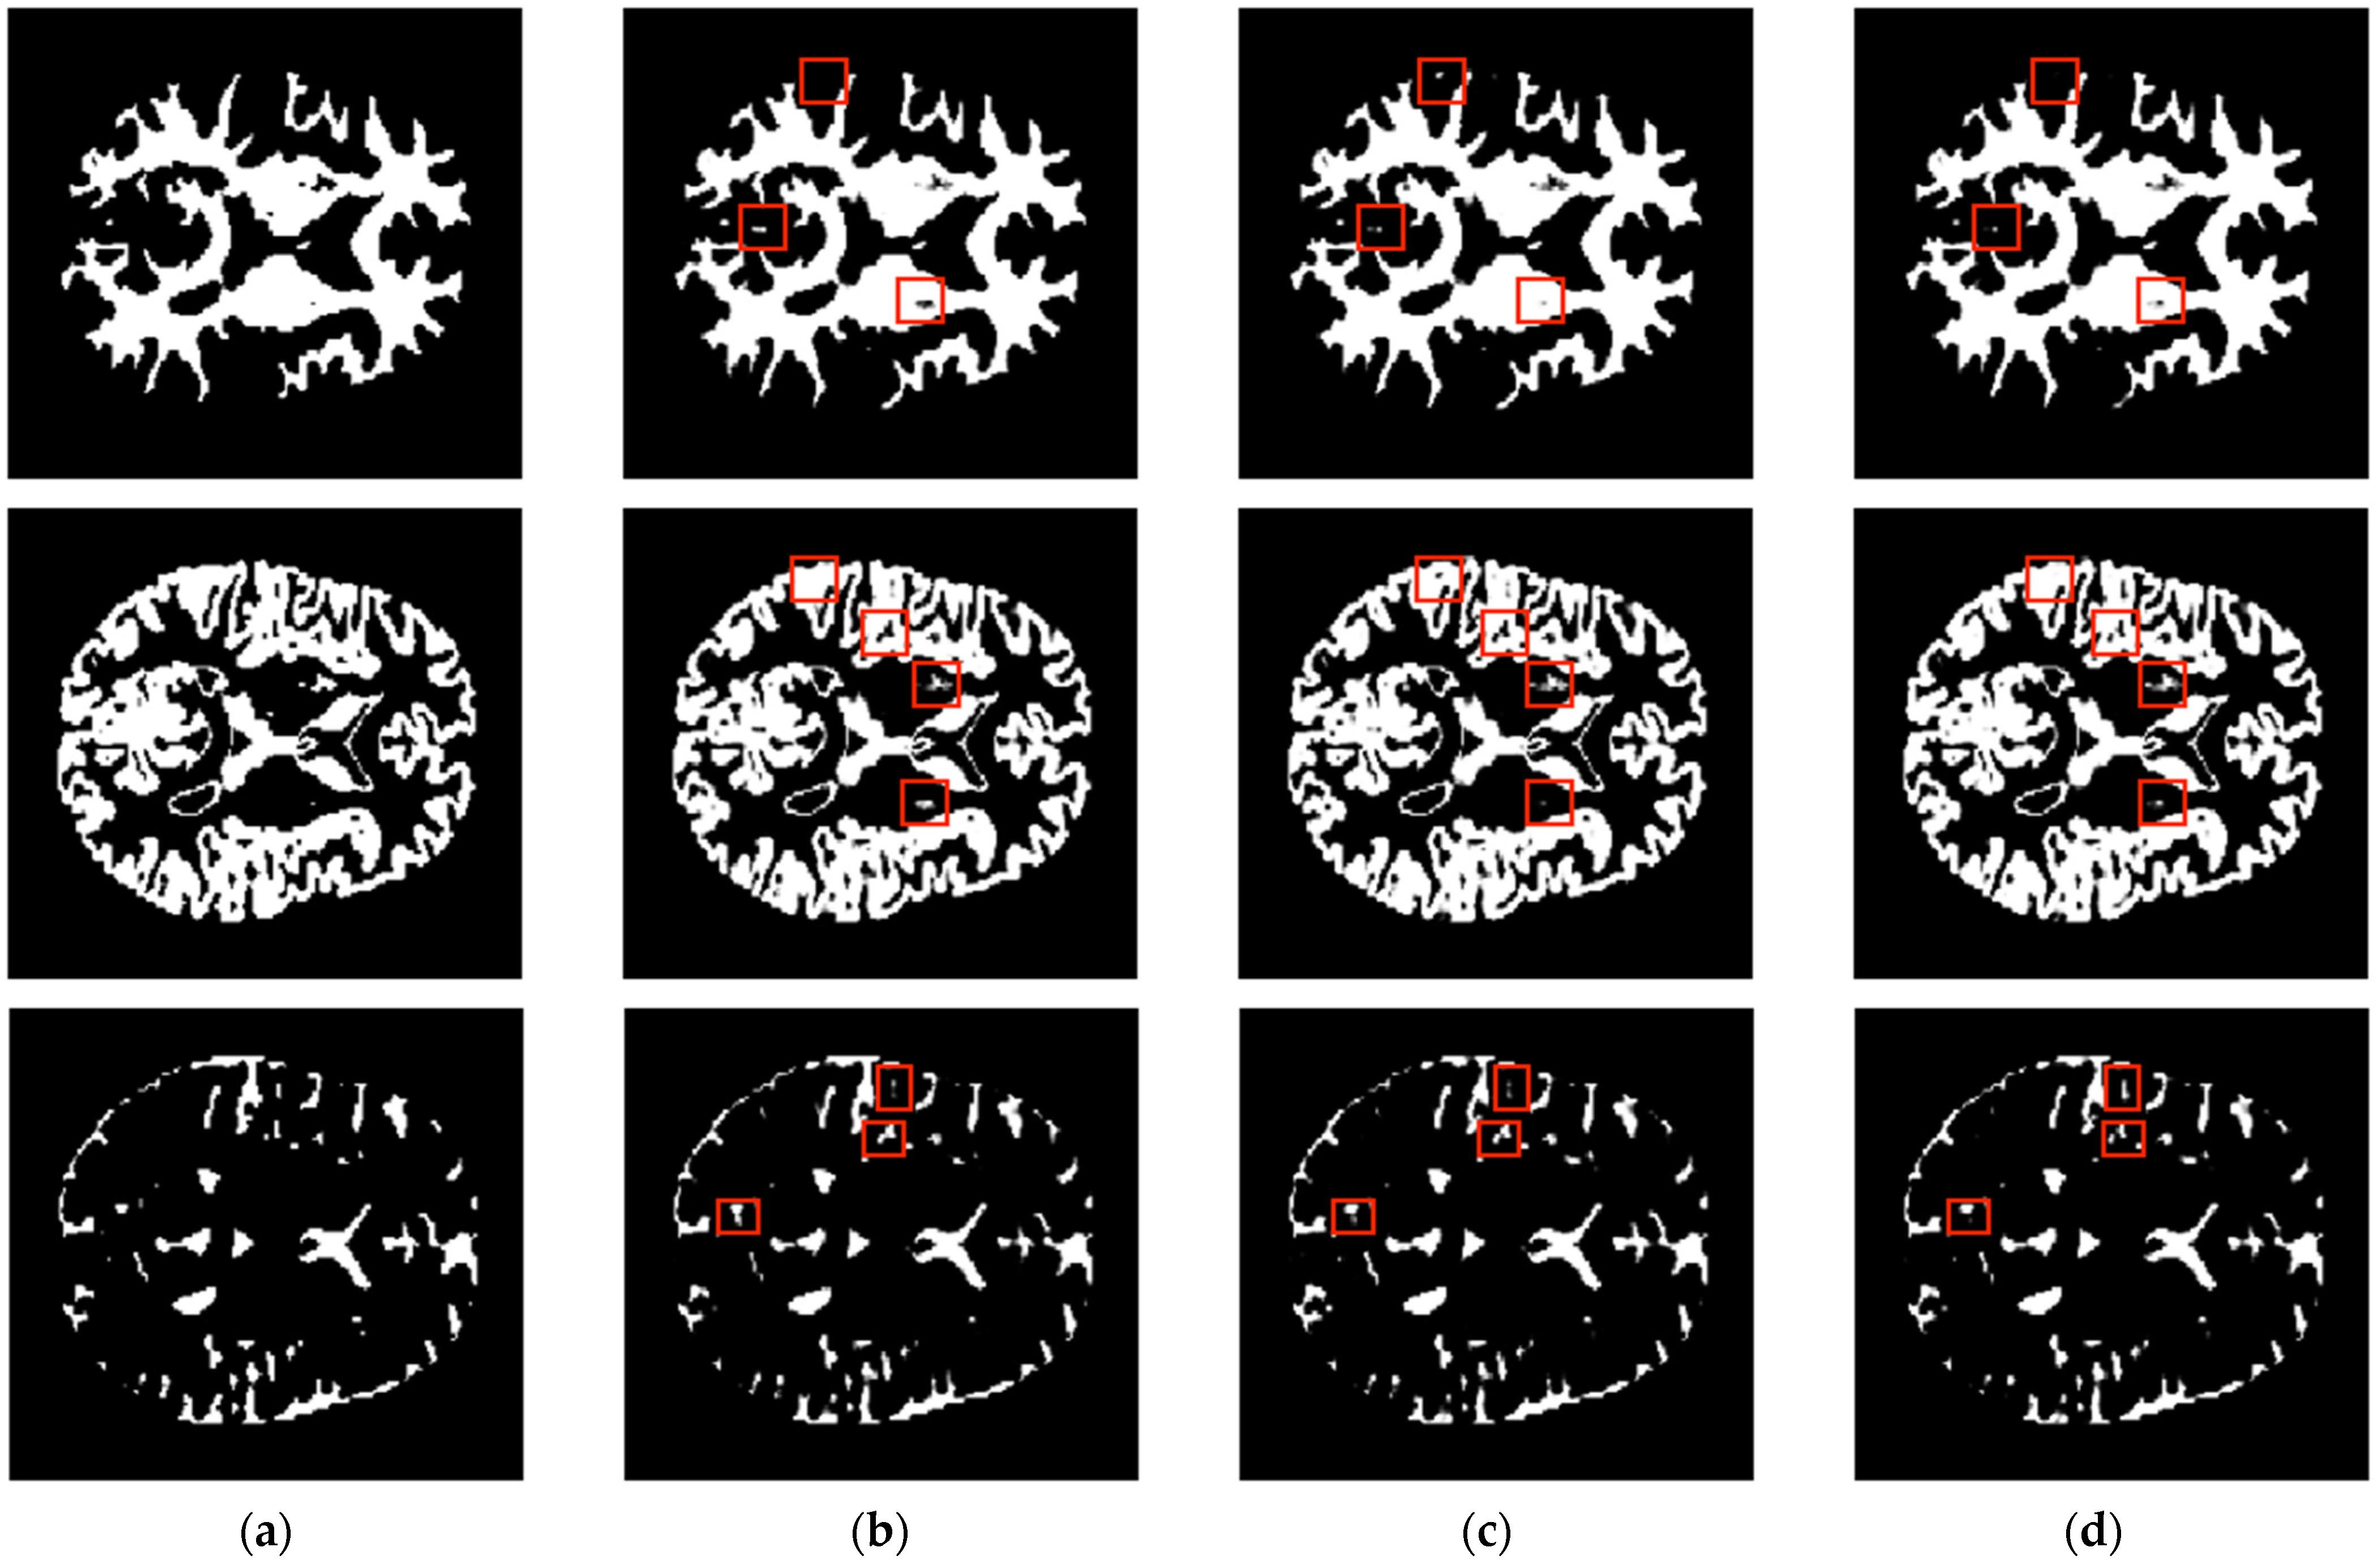

3.1. Analysis and Comparison with Single-Slice and Multiple-Slice Input UNet